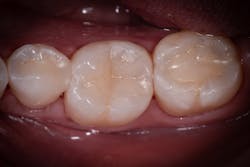

A 27-year-old patient was referred to me due to discomfort associated with dentinal hypersensitivity secondary to erosion on his posterior teeth (figure 1 above: Initial presentation. Note the exposed dentin due to erosion). His former dentist suggested crown lengthening due to inadequate space for full-coverage crowns.

After a thorough evaluation of his clinical presentation, radiographs, and intraoral scan, it was evident that the discomfort was due to exposed dentin. The intraoral scan confirmed there was adequate interocclusal space to restore the eroded tooth structure with a minimally invasive approach (figure 2). All options were reviewed with the patient, and it was mutually agreed upon to address his chief complaint in this manner. Proper isolation is critical for reliable bonding.

In this case, lateral access was achieved by the preparation of the adjacent teeth as part of the proposed treatment plan. Early caries lesions that are noted on radiographs that are not accessible in cases such as this one can be accessed by placing an orthodontic spacer. This patient was restored with direct composite bonding (figure 5) and these restorations have proven to have a favorable long-term outcome (figure 6).